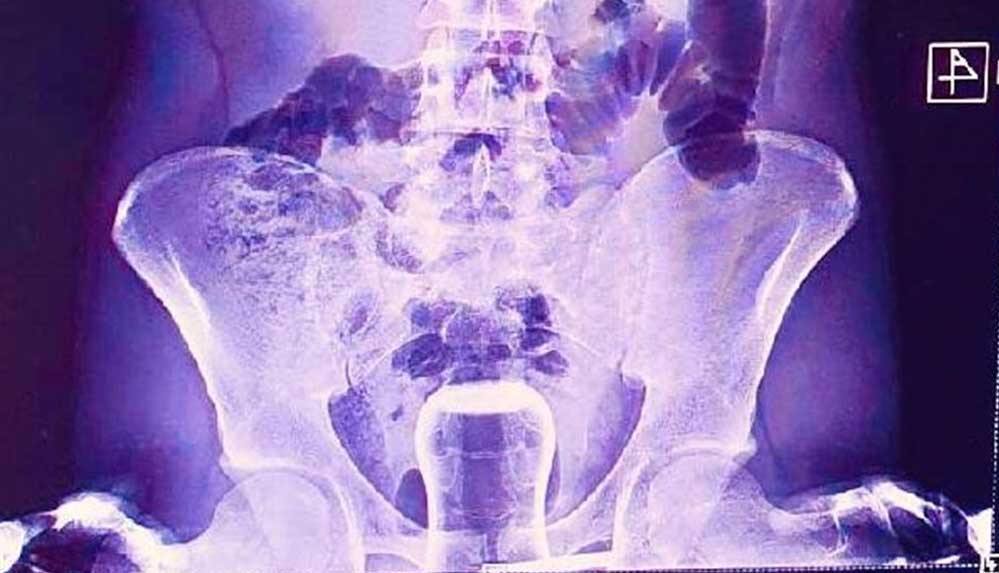

Acil serviste hastanın çekilen röntgeninde anüs bölgesinde çay bardağı görüldü.

Bu kişi genel cerrahi servisinde ameliyata alındı.

Çay bardağı, uzman doktorlar tarafından gerçekleştirilen operasyonla çıkarıldı.